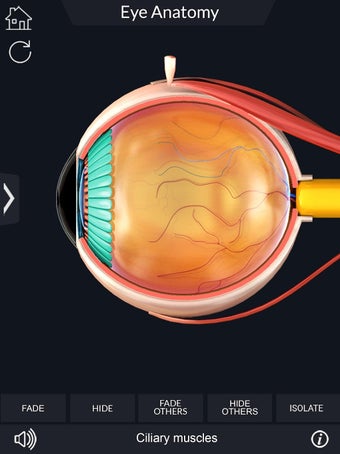

Изучите в деталях человеческий глаз и его анатомию с помощью этого простого в использовании бесплатного приложения для Android. Он позволяет масштабировать и вращать на 360° вокруг высокореалистичной 3D-модели глаза, а также рисовать на экране или прослушивать звуковое произношение каждого термина.

Вы можете выбрать X- просмотр луча, скрытие и отображение отдельных частей глаза, а также рисование или белый цвет на экране и обмен снимками экрана, звуковое произношение для всех анатомических терминов и многое другое.

Каждая часть разделена на отдельный вид, где вы можете можно увидеть название детали и ее расположение на глаз.